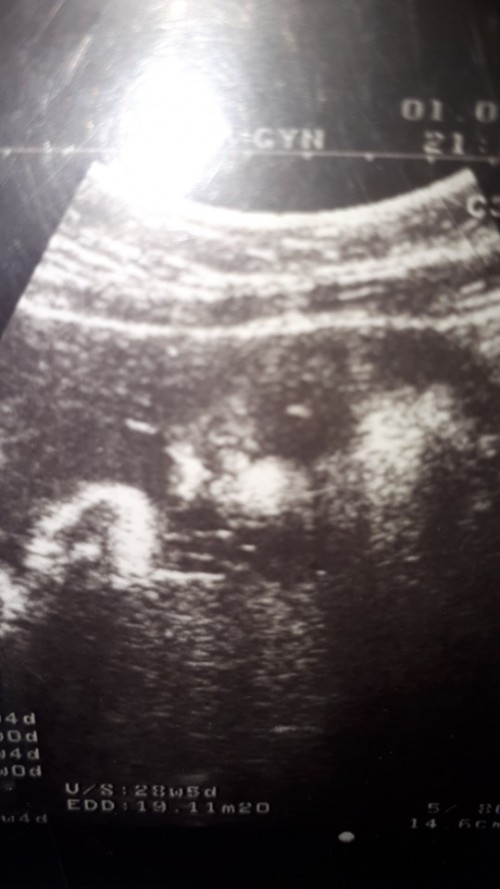

ผู้ชาย 28 week ค่ะ 😊